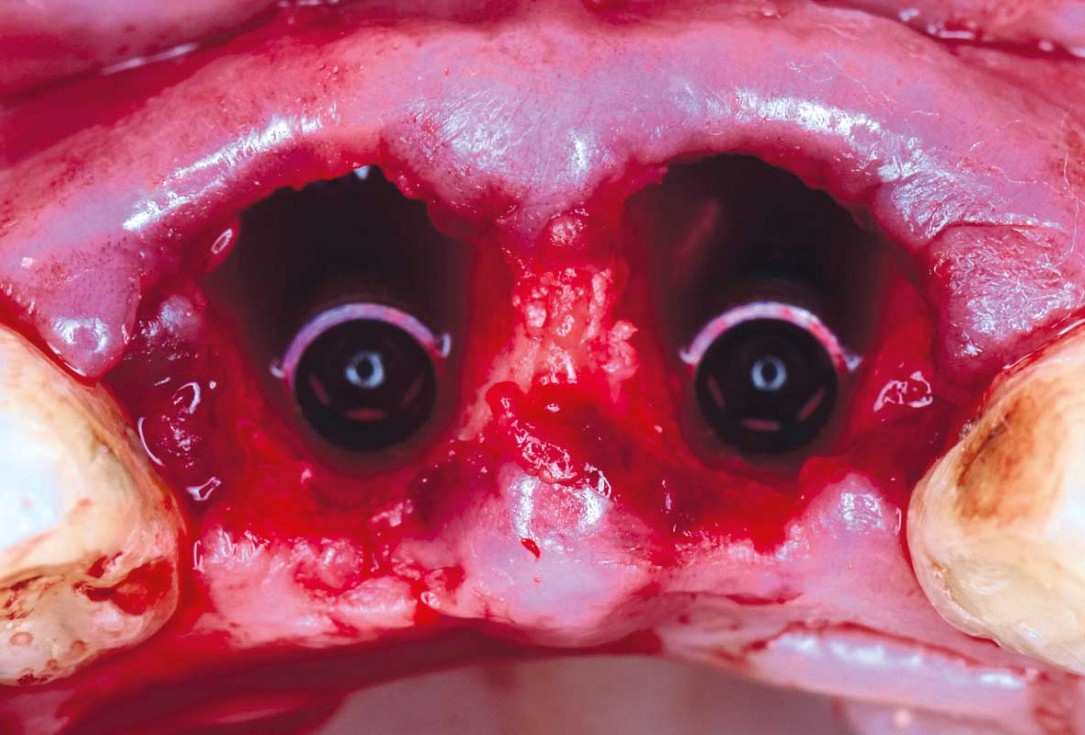

04/22 - Immediate implants are placed after extractioncerabone® and mucoderm® for immediate implantation in the aesthetic area - Dr. D. Robles